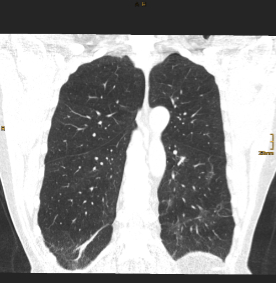

Pressebilder frei zum Download: ©Univ.-Klinik für Radiologie Innsbruck

BU: CT Thorax eines Teilnehmers während des stationären Aufenthalts (Bild links) und nach einem Jahr (Bild rechts) im Vergleich. Die initial ausgeprägten Gewebsvermehrungen sind deutlich rückläufig, jedoch zeigen sich residuell noch feine lineare Verdichtungen in beiden Unterlappen.

Eine aktuelle, kürzlich im angesehenen Fachjournal Radiology veröffentlichte Ein-Jahres-Folgestudie des Teams um den Radiologen Gerlig Widmann liefert nun neue Erkenntnisse zum Verlauf von Lungenveränderungen in der Computertomographie (CT) nach COVID-19. „In unserer viergeteilten Kohorte* betreffend den Schweregrad des initialen Verlaufes waren bei mehr als der Hälfte der Teilnehmer:innen auch noch zwölf Monate nach Krankenhausentlassung subtile Veränderungen im CT nachweisbar. Auch wenn eine Mehrheit dieses Anteils zumindest schwer erkrankt war, sind wir von diesem Ergebnis doch ein wenig überrascht. Der über 60-jährige männliche Patient mit kritischem Krankheitsverlauf trägt unseren Untersuchungen zufolge jedenfalls das größte Risiko, auch ein Jahr nach Covid-19 noch Lungenveränderungen im CT zu zeigen“, erklärt Radiologin und Erstautorin Anna Luger. Insgesamt wurden vier CT-Verlaufskontrollen der Lunge durchgeführt, von anfangs 142 Proband:innen konnten nach einem Jahr noch 91 Teilnehmer:innen in die Studie eingeschlossen werden.

Im Detail zeigten 34 Prozent der Teilnehmer:innen oberflächennahe netzartige Verdichtungen der Lunge, geringe Milchglastrübungen oder beides, bei 20 Prozent der Teilnehmer:innen waren ausgedehnte Milchglastrübungen, oberflächennahe netzartige Verdichtungen, Bronchialerweiterungen und mikrozystische Veränderungen feststellbar, die eventuell auf Vernarbungsprozesse hindeuten. „Aus radiologischer Sicht lässt sich noch nicht abschätzen, wie sich diese strukturellen Lungenveränderungen zeitlich weiter verhalten“, so der Leiter der Radiologie in der interdisziplinären Studiengruppe, Gerlig Widmann. Drei Szenarien seien jedoch vorstellbar: Die Veränderungen bilden sich langsam vollständig zurück, die Veränderungen halten an und es entwickeln sich stabile Vernarbungen, oder das Lungengewebe wird zunehmend fibrotisch (Bindegewebsvermehrung) und es kommt begleitend zu kontinuierlich zunehmenden klinischen Symptomen. „In jedem Fall“, so Widmann, „werden wir den Verlauf gemeinsam mit unseren klinischen Partnern weiter wissenschaftlich begleiten“.